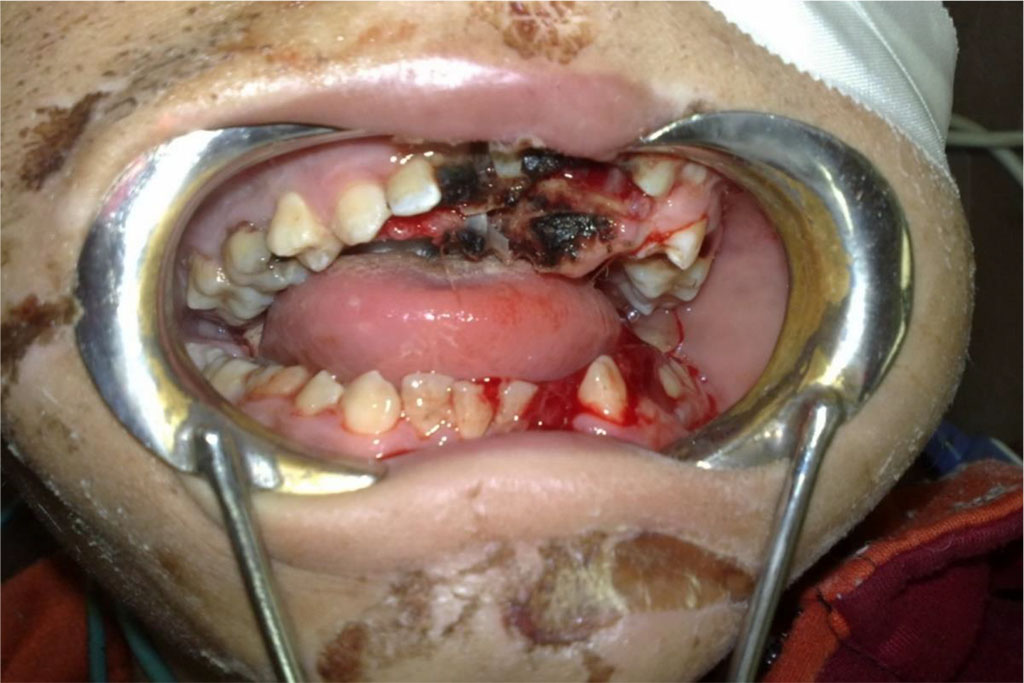

Facial examination: Mild facial oedema, multiple facial abrasions and contusions. Oral malocclusion, lost maxillary central, left lateral incisors and canine, tender mobile maxilla; Le fort I fracture (Table 1), soft palatal tear (Figure 1) and a complex displaced left parasymphysial mandibular facture with lost left mandibular lateral incisor (Table 2).

Figure 1: The maxillary Le Fort I and the left parasymphysial mandibular fractures.